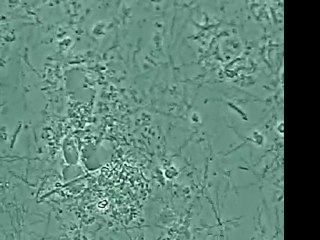

Le laser permet de supprimer les varicosités (petits vaisseaux disgracieux) de la peau sur le visage et sur corps.